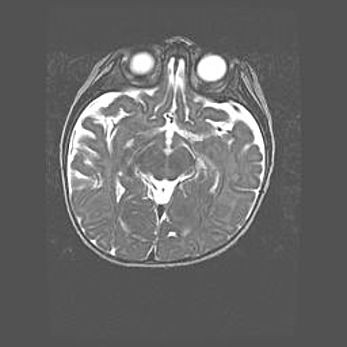

Лейкомаляция с кистозно-глиозной дегенерацией головного мозга.

Возраст: 2 месяца 25 дней

Вес: 6400 г

Окружность головы: 40 см

Срок гестации: 41 неделя

Лейкомаляцию относят к ишемически-гипоксическим повреждениям головного мозга, диагностируемым у новорожденных. При лейкомаляции в головном мозге обнаруживают очаги некроза, возникшие после тяжелой гипоксии и нарушения кровотока. В процессе морфогенеза очаги проходят три стадии: 1) развития некроза, 2) резорбции и 3) формирования глиозного рубца или кисты. Перивентрикулярная лейкомаляция (ПЛ) встречается примерно в 12% случаев среди новорожденных, обычно – у недоношенных детей, причем, частота ее зависит от массы, с которой младенец появился на свет. Наибольшее число малышей страдает лейкомаляцией, если масса при рождении 1500-2500 г.